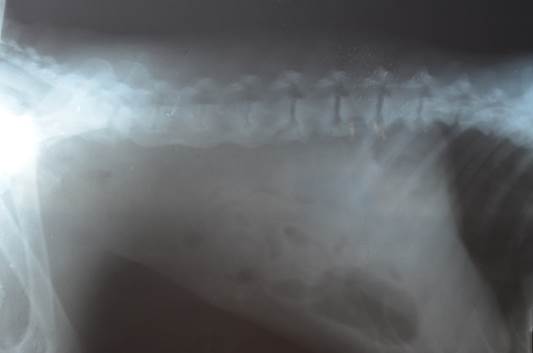

Диагноз дискоспондилита собак основывается на характерный рентгенологических изменениях совместно с подходящей историей болезни и данных обследования.

Радиографическое исследование при дискоспондилите выявляет коллапс межпозвоночного пространства в зоне поражения, лизис концевых пластинок позвонков и различные компоненты пролиферации и склероза концевых пластинок. Поражения при дискоспондилите собак могут быть как единичными так и множественными, чаще всего инфекционный процесс развивается в пояснично-крестцовом соединении (L7-S1), затем по частоте встречаемости поражений идут диски грудопоясничного отдела, и реже всего дискоспондилит развивается в шейных отделах позвоночника.

Радиографические изменения на начальных стадиях дискоспондилита обнаруживаются не всегда, они могут запаздывать на 2-4 недели. У пациентов с признаками дискоспондилита, но без характерных рентгенологических изменений – болезнь все же может присутствовать, в таких случаях, более ценным методом диагностики может служить компьютерная и магниторезонансная томография.